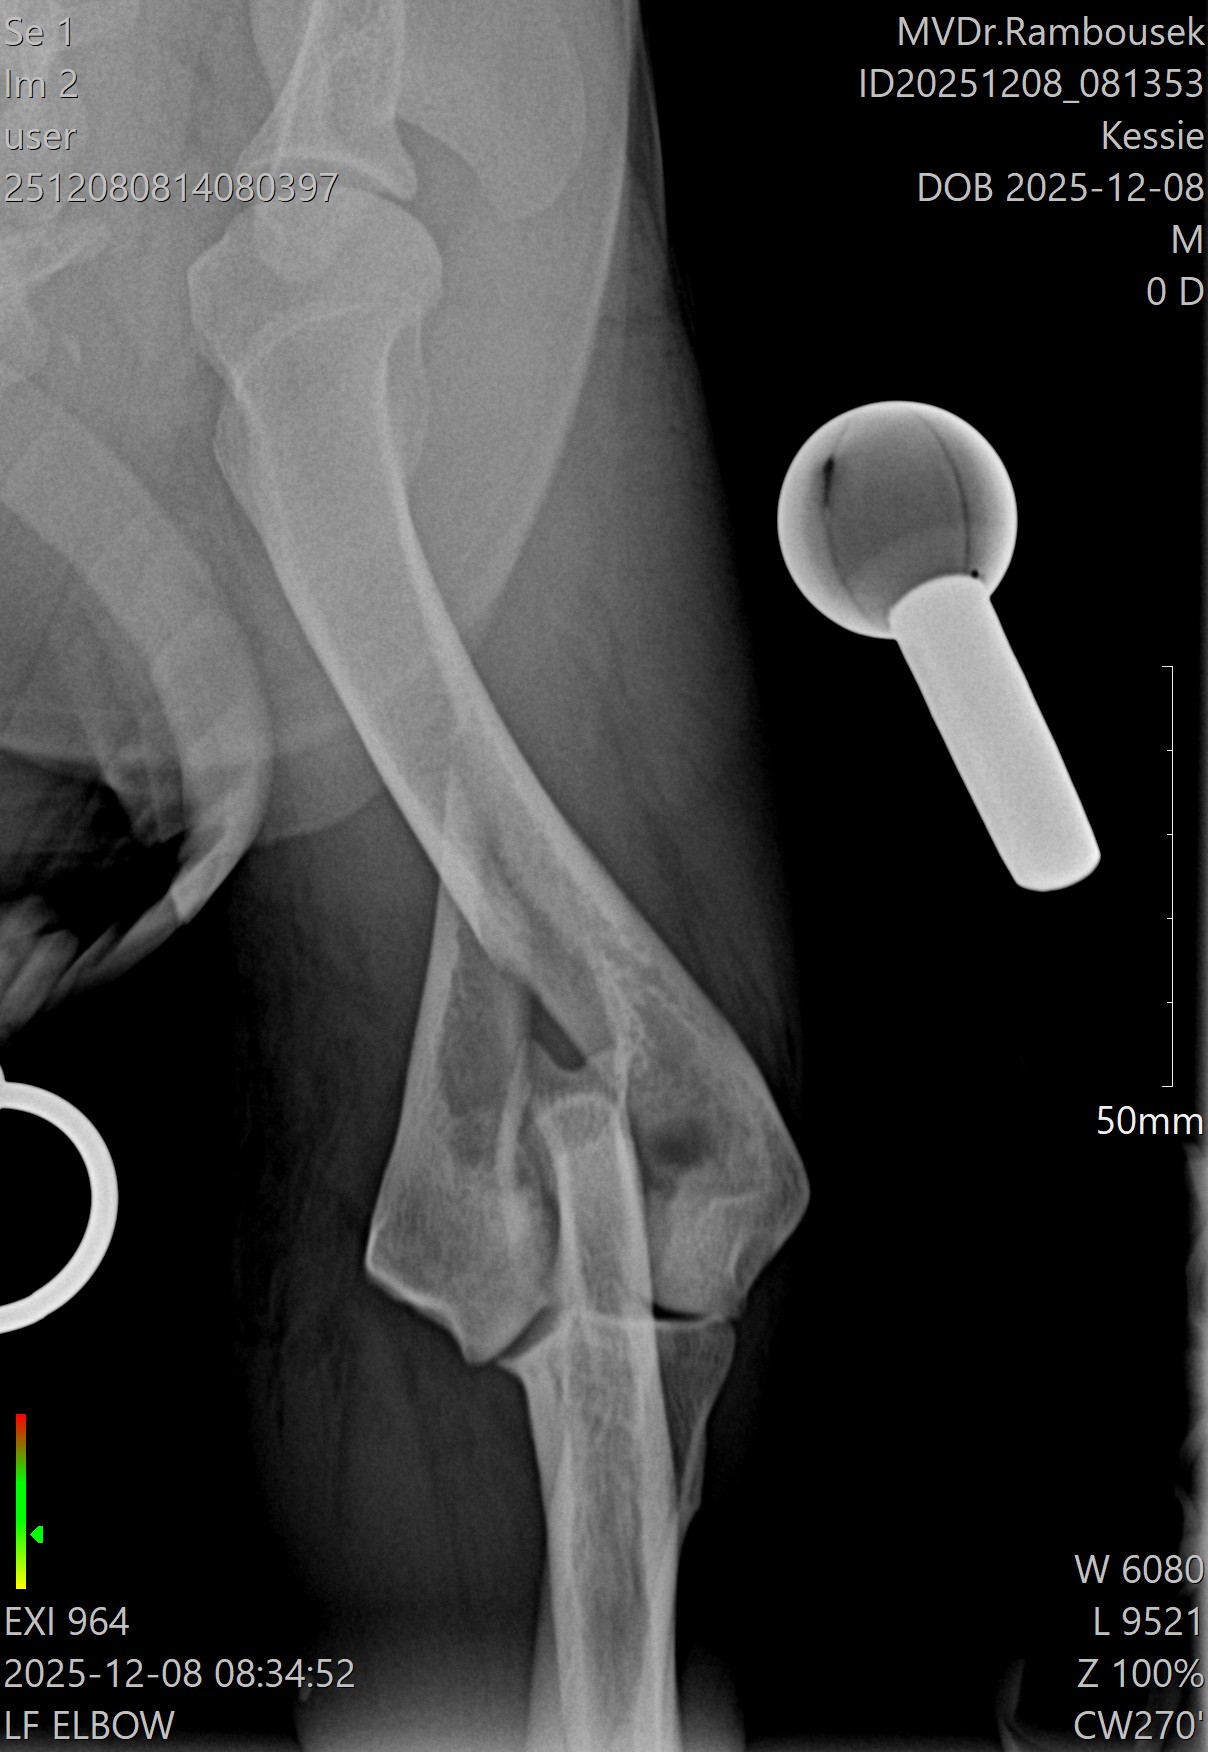

Fraktura pažní kosti - mediální kondylus

Případy z praxe

Akutní

případ